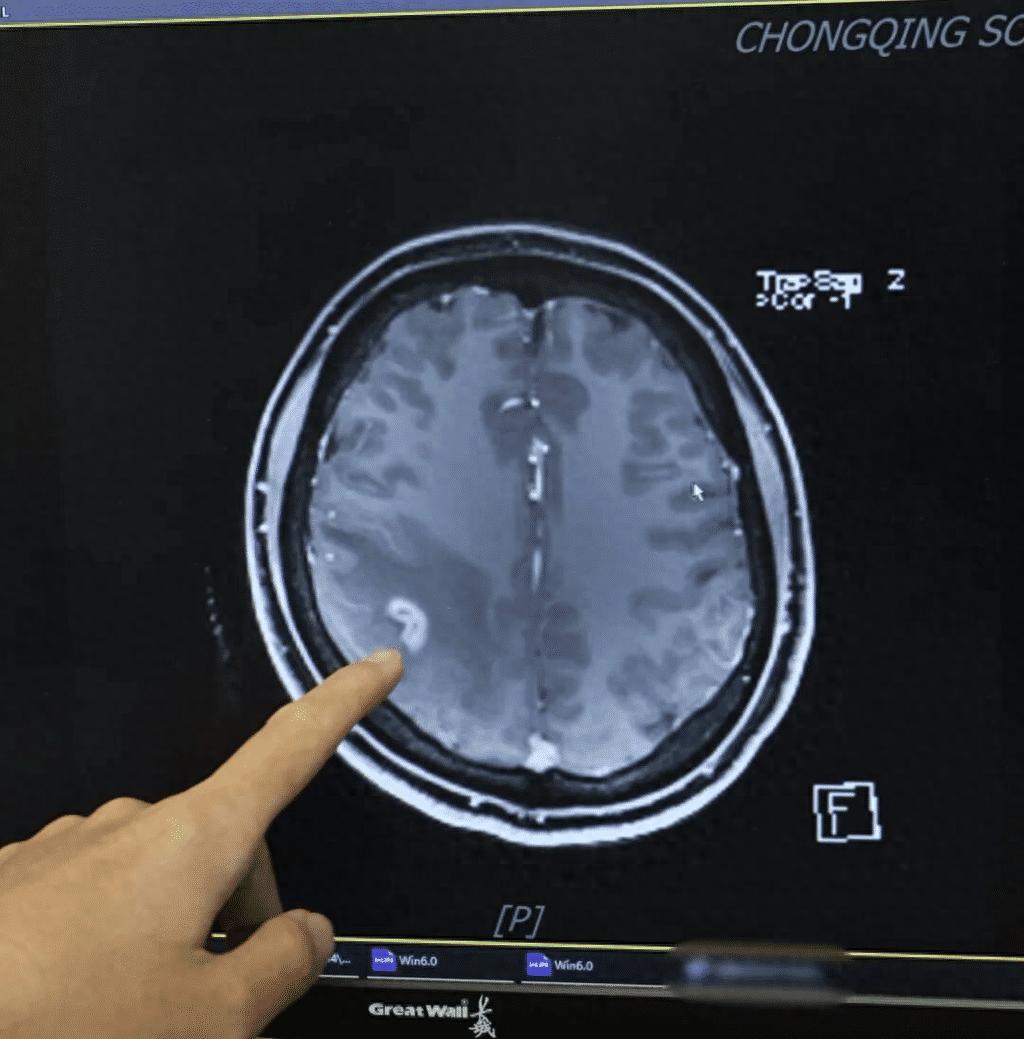

女子多年肢体麻木开颅抓出3厘米活虫!

女子多年肢体麻木开颅抓出3厘米活虫!“太感谢了,这么多年终于找到了病因!”3月26日,记者从陆军军医大学西南医院获悉,该院神经内科日前收到了一面来自患者的锦旗,感谢团队帮助她治好了脑部寄生虫感染。患者王女士回忆(化名),5年前她先是突然出现...